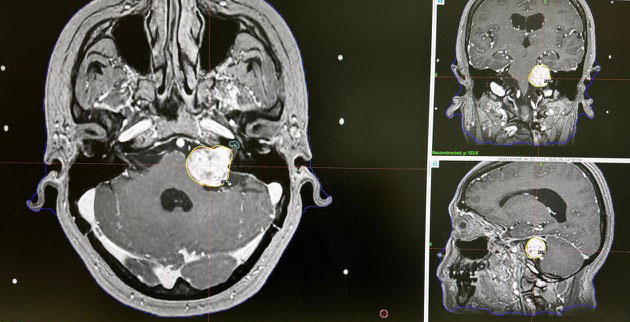

Dr. Ujwal Yeole performs intraoperative neuromonitoring for his patients, including cranial nerve monitoring, cortical mapping, subcortical stimulation, and speech and motor area mapping. These techniques help ensure the safety and effectiveness of neurosurgical procedures.

By continuously monitoring brain and spinal cord functions during surgery, Dr. Yeole can reduce the risk of neurological damage and preserve critical functions such as movement, sensation, and speech.